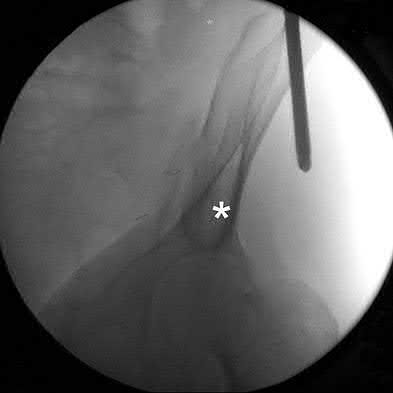

Figures A and B demonstrate a distal third tibial shaft fracture with simple intra-articular extension. The axial and coronal CT cuts in Figures C and D further clarify the articular injury. Illustrations A and B demonstrate a comminuted distal third tibial fracture with simple intra-articular extension. Illustrations C and D are fluoroscopic images of the same injury after intramedullary nailing and percutaneous fixation of the articular component.